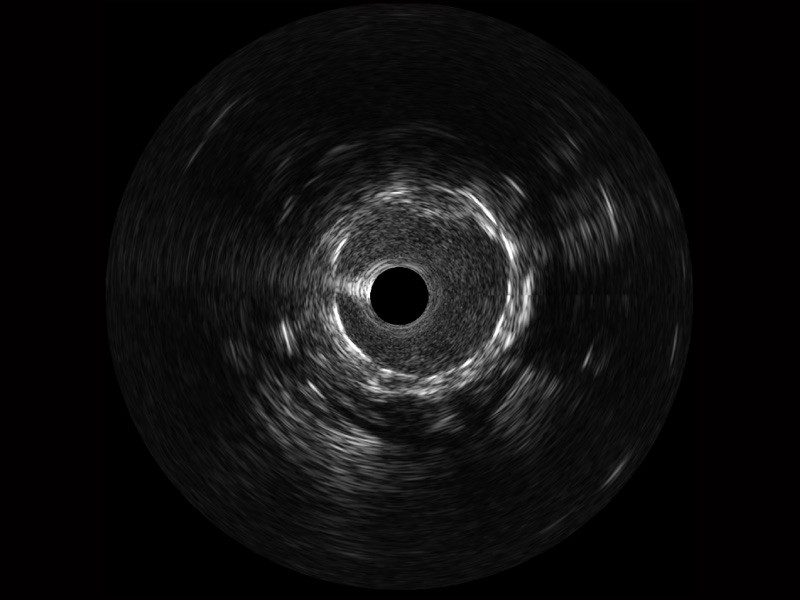

传统IVUS图像

对比传统IVUS导管成像,16877太阳集团宽频IVUS图像的近场支架梁显影更细腻,远场中膜外血管仍清晰可辨,兼顾远中近,兼顾分辨力与穿透深度